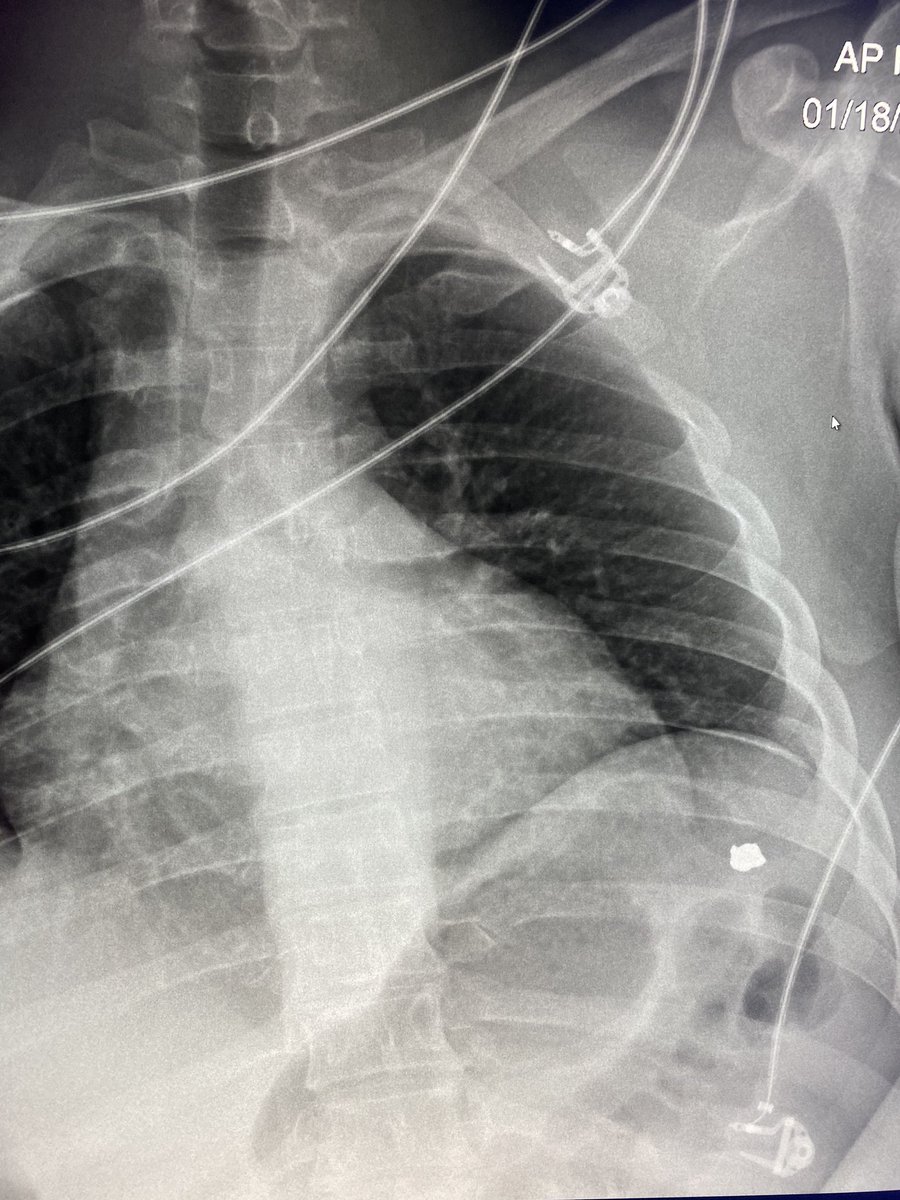

When it rains, it pours.

#radres, 2 complications to placement of the R central venous catheter on this XR... arterial placement AND pneumothorax. Satisfaction of search!#FOAMed#FOAMRadpic.twitter.com/wl1qBZIEbp